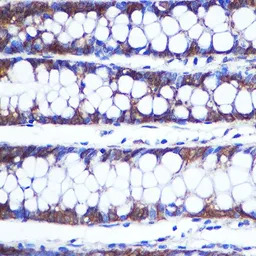

IHC-P analysis of human colon tissue using GTX66397 TOP1MT antibody.

Dilution : 1:100